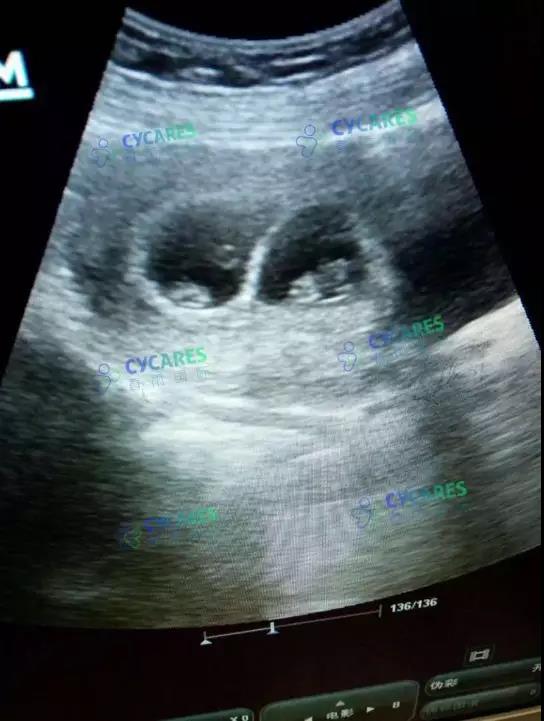

2018年1月4日,蓝姐发了B超报告,两个胎囊、胎心胎芽都正常。

微信图片_20180921173710.jpg